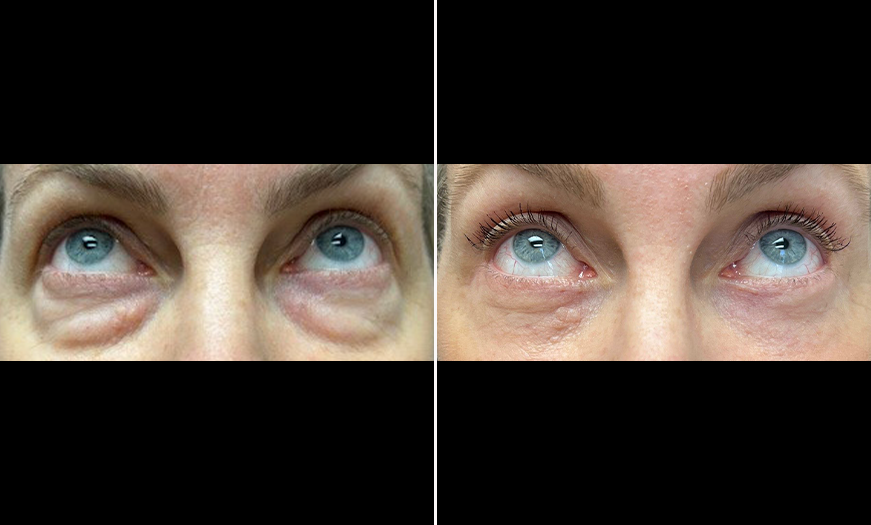

CANTHOPEXY PERFORMED WITH LOWER BLEPHAROPLASTY

Instead, the lateral tendon is reinforced, usually by being tightened with sutures.

Visually, the effect is almost unnoticeable, and this procedure is often done alongside lower blepharoplasty to prevent the eyelid from sagging.

Price: Usually about half the cost of a canthoplasty. (€800-€3,000)

It’s a minimally invasive procedure.

CANTHOPEXY PERFORMED WITH LOWER BLEPHAROPLASTY